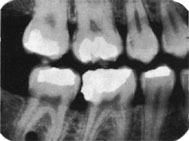

Radiografía de aleta mordible (Bite-Wing)

La técnica tiene ventajas con respecto a la radiografía periapical, debido que  reduce el tiempo de exposición a la radiación  y disminuye los costos y honorarios.

La cabeza del paciente se coloca de manera que el plano de oclusión quede paralelo al del piso. El rayo central se dirige al punto de contacto de los dientes superiores con los dientes inferiores y paralelo a sus superficies proximales, con el tubo formando un ángulo de 5 a 10º por encima del plano horizontal.

Para los dientes posteriores es deseable tomar dos vistas de cada lado:

• una en la que la película  se coloca más atrás para incluir el espacio inter-proximal  entre el segundo y el tercer molar,

• y la otra lo bastante adelante como para tomar la cara distal del canino. Solo necesita cuatro películas para el diagnóstico de caries en todos los sectores posteriores.

Técnica de Bite-Wing

Debe tener en cuenta el tiempo de exposición y  el kilovoltaje  del equipo radiográfico, como la sensibilidad de la película radiográfica.

A modo de ejemplo con una película tipo  Speed y un  kilovoltaje de 65;  el tiempo de exposición es de 0.8 segundos en zona de molares. En Premolares y Caninos 0.7; y en Incisivos 0.6 segundos.

A mayor kilovoltaje Menor tiempo de exposición